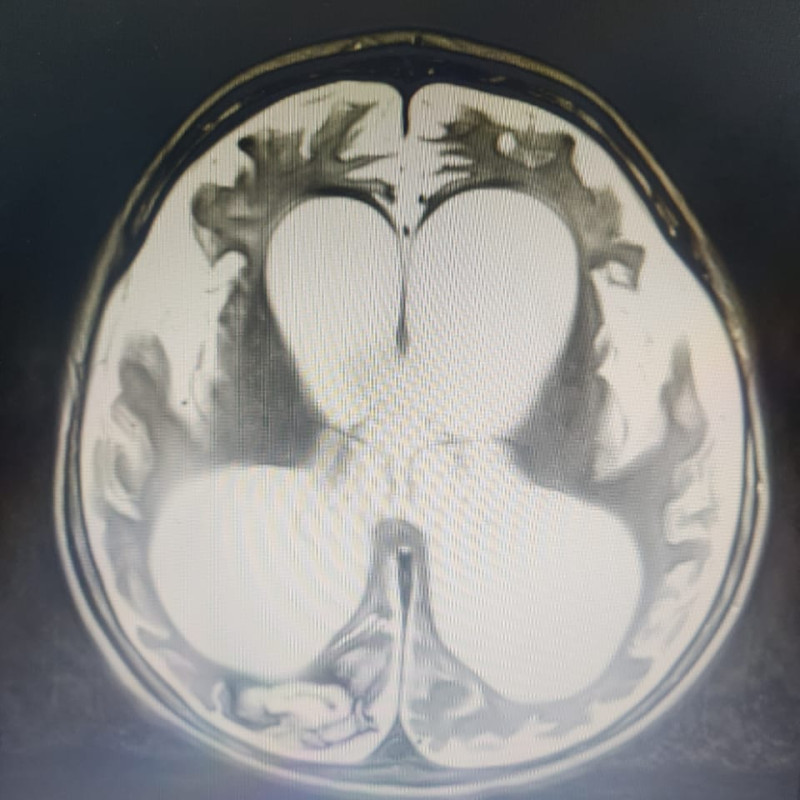

Saat usianya 8 bulan, Ryuga sudah didiagnosa kerusakan otak yang membuatnya tidak bisa mengontrol gerakan tubuh dan ototnya (Cerebral Palsy), serta didiagnosa infeksi pada bagian belakang tenggorokannya (Faringo).

Saat usianya 8 bulan, Ryuga sudah didiagnosa kerusakan otak yang membuatnya tidak bisa mengontrol gerakan tubuh dan ototnya (Cerebral Palsy), serta didiagnosa infeksi pada bagian belakang tenggorokannya (Faringo).